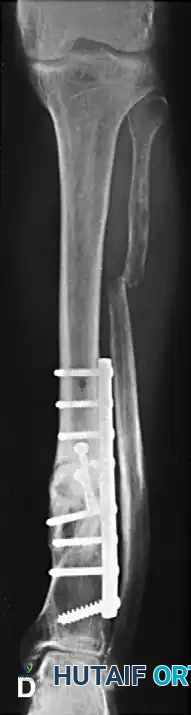

1. Temporary Fixation: The corrected position is provisionally held with reduction clamps and Kirschner wires. Fluoroscopy confirms the restoration of the mechanical axis in both the AP and lateral planes.

2. Definitive Fixation: A heavy-duty dynamic compression plate (or locking compression plate depending on bone quality) is contoured to the corrected anatomy. Interfragmentary lag screws are placed orthogonally across the oblique osteotomy to provide absolute stability and primary bone healing. The plate is then secured with bicortical screws.